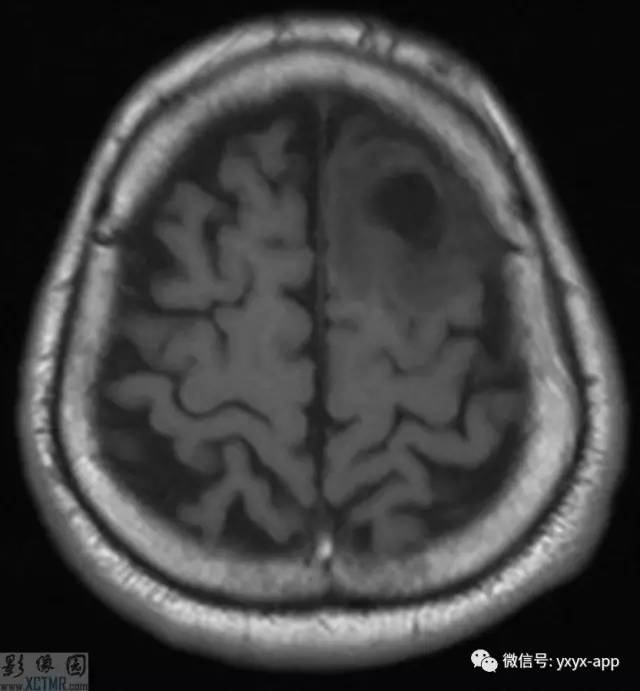

CT:左侧额叶一囊性肿块伴水肿。MRI:轴位T1WI和T2WI显示左侧额叶一囊性肿块伴周围脑实质显著水肿,但无明显占位效应。T1WI增强图显示病变为分叶环形囊状肿块伴周围脑实质水肿,囊壁环形强化,囊内及周围水肿区无强化。

影像学表现取决于感染的位置以及感染的阶段。此病例在胶状水泡阶段,寄生虫的死亡引起明显的炎性反应。影像学表现包括:围绕囊性病变的血管源性水肿;增强后环状增强;T1WI胶状囊性病变周围为低信号;有时可见T1WI头节高信号影。